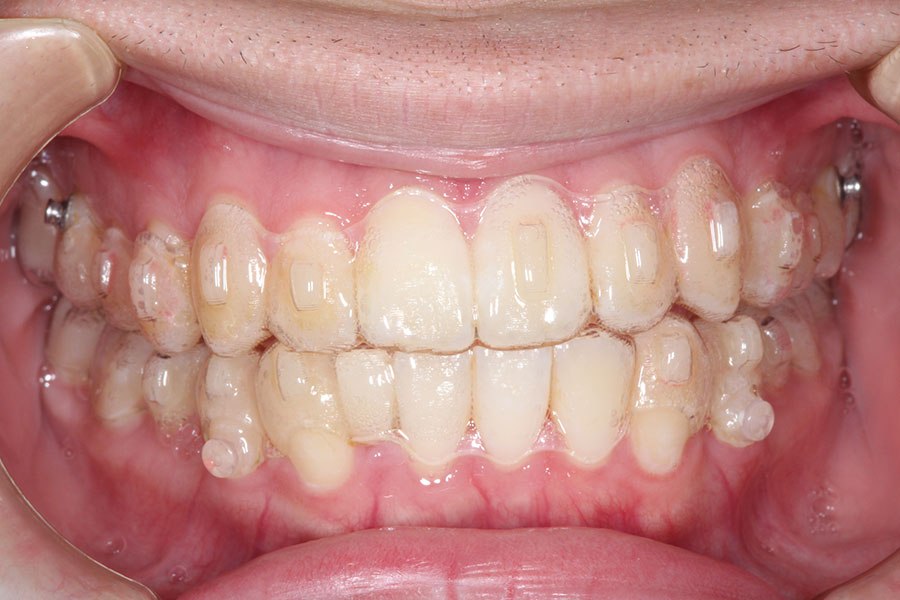

Before -正面-

After -正面-

Before -側面-

After -側面-

| 施術内容 | ワイヤー矯正から、目立ちにくくメタルフリーなインビザラインへ変更しました。 金属アレルギーの不安が軽くなり、取り外しできることで清掃性も向上。見た目も自然で、治療中のストレスが少ない矯正方法です。 |

|---|---|

| 治療期間 | 2年間 |

| 費用 | インビザラインフル 767,800円 リテーナー 30,000円 |

| リスク・副作用 | 治療にともない、歯の破折や歯質の削合、場合によっては抜歯が必要となることがあります。また、金属や補綴物を除去する際に、完全に除去できない場合もあります。 |